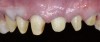

Fig 20. Postoperative occlusal view of maxillary arch with full-contour monolithic high-translucent zirconia restorations on all teeth.

Figure 20

A 40-year-old patient presented with the chief complaint: “My teeth are cracking, and I would like to have my original bite.” Dental findings included Class I occlusion with slight misalignment between teeth Nos. 8 and 9. Generalized severe occlusal wear and slight Class I mobility of teeth Nos. 23 to 26 were noted. Caries lesions were found on teeth Nos. 2, 4, 6, 8, 9, and 14 and abfraction lesions on teeth Nos. 4, 5, 10, 11, 13, 20, and 21. Figure 1 through Figure 3 depict the preoperative situation. Full-mouth rehabilitation was suggested. The goals for the restorative treatment were management of erosive etiology, conservation of tooth structure, and long-term protection of the restorations. A diagnostic wax-up was instrumental in determining functional and esthetic treatment goals and establishing new anterior guidance (Figure 4). A comprehensive, step-by-step treatment approach was applied, which, after periodontal pretreatment, caries control, and provisionalization, included definitive preparation (Figure 5) and restoration of the maxillary anterior teeth to establish anterior occlusal guidance. CAD/CAM–fabricated full-contour monolithic high-translucent zirconia crowns (Katana™ UTML Ultra Translucent Multi-Layered, Kuraray Noritake Dental, kuraraynoritake.com) were fabricated (Figure 6 and Figure 7) and cemented with self-adhesive resin cement (Panavia SA, Kuraray Noritake Dental). Figure 8 demonstrates the cemented anterior crowns and refined conservative preparations of posterior teeth, which were performed with minimal tooth-structure removal. High-translucent monolithic zirconia onlays and crowns were fabricated (Katana Zirconia UT, Kuraray Noritake Dental) (Figure 9 to Figure 12). The posterior restorations were adhesively bonded following the APC zirconia-bonding concept. APC-Step A involved air-particle abrasion with 50-μm aluminum oxide at 1.5 bar with a chairside microetcher (Figure 13), followed by application (APC-Step P, Figure 14) of a special ceramic primer (ClearfilTM Ceramic Primer, Kuraray Noritake) with adhesive phosophate monomers (MDP). Relative moisture and contamination control was achieved with cotton rolls and retraction cords. Rubber dam placement, which is always preferred, was difficult in this situation. The enamel surfaces of the abutment teeth were selectively etched (Figure 15) with 35% phosphoric acid (K-Etchant Gel, Kuraray Noritake Dental) and the dentin conditioned (Figure 16) with a self-etch dentin primer (Panavia V5 Tooth Primer, Kuraray Noritake Dental). A dual-cure adhesive resin (Panavia V5 Paste Universal, Kuraray Noritake Dental) was dispensed directly into the restorations with an automix syringe. The restorations were inserted, and excess cement was carefully removed (Figure 17 and Figure 18) before light polymerization (Figure 19). Postoperative views depict the treatment outcome (Figure 20 to Figure 22).